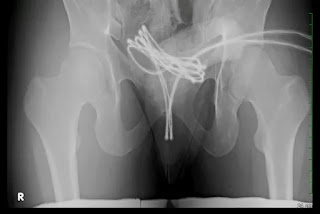

Médicos americanos descreveram, na edição de fevereiro da revista médica Cureus, o caso de um estudante universitário de 21 anos que inseriu um cabo USB na própria uretra para obter prazer s3xual. Ao perceber que o fio estava preso e que não conseguiria removê-lo por conta própria, o homem procurou ajuda médica em um hospital.

Durante a consulta, ele revelou aos médicos que não foi a primeira vez que praticou o ato. O jovem disse que já havia usado objetos como cotonetes e cabos de aço para estímulo s3xual. A prática é conhecida como sondagem uretral e consiste na introdução de objetos no canal da uretra – o tubo que conduz a urina da bexiga para fora do corpo –, com o objetivo de sentir prazer.

“A autoinserção de objetos na uretra por motivos s3xuais ou outros é rara, mas pode causar danos sérios”, relatam os autores do artigo, que são da Faculdade de Medicina da Universidade Drexel, nos Estados Unidos.